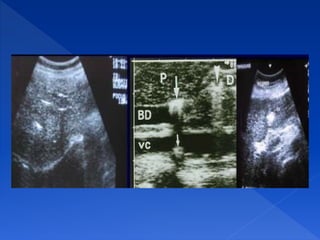

La imagen ecográfica muestra

una zona oscura detrás de una

estructura hiperecogénica.

Es una interfase muy reflexiva y

casi toda la energía del haz

sónico incidente sobre ellas se

reflejará.

SOMBRA ACÚSTICA POSTERIOR

Zonas sin ecos que aparecen

detrás de estructuras que reflejan

todos los ultrasonidos

REFUERZO ACÚSTICO POSTERIOR

Aumento en la amplitud de los ecos que se

generan tras atravesar una estructura

anecoica.

La imagen ecográfica muestra una

estructura anecoica e inmediatamente

detrás de esta aparece una zona

hiperecogénica.

Se da detrás de estructuras que contienen

líquido. Ejemplo fisiológico: la vesícula

biliar, un vaso. Ejemplo patológico: un

quiste, un derrame